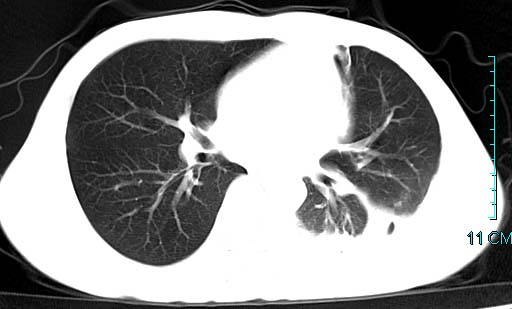

以下是引用qian在2006-3-28 14:32:00的发言:[br]左肺下叶大片状阴影,密度不均,见有条片影和空洞及气液平,少量胸腔积液伴有胸膜增厚,从图像看积液密度比水的密度高,结合病史,考虑左下肺化脓性炎症伴有脓胸。

以下是引用wawaquan在2006-3-28 22:25:00的发言:[br]左上肺舌段多发斑片影。结合“男24y咳嗽咳痰气促伴高热(38.5--39.5)20多天”及穿刺史,[br]考虑1 左下肺化脓性炎症;2脓胸。

以下是引用乡医在2006-3-28 18:37:00的发言:[br]左侧多发液气平面结合患者男24y咳嗽咳痰气促伴高热(38.5--39.5)20多天,查胸水:ldh239.3,总蛋白59.19,tb-ab阴性,利凡它试验+,红c2.7*109,白c1.08*109,分类淋巴92%分叶8%,考虑1脓胸2肺隔离征感染